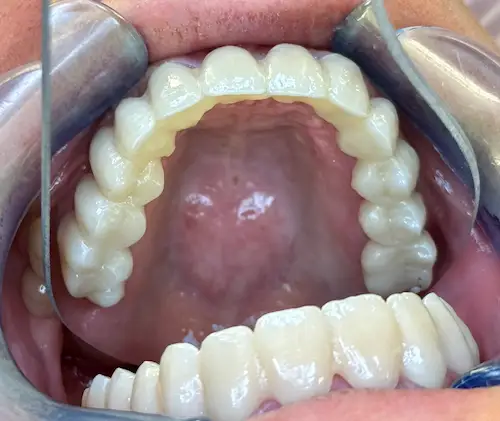

Der chirurgische Eingriff im Detail

Der Tag der Operation ist gekommen: Im ersten Schritt werden die noch vorhandenen Zähne gezogen sowie die Wurzeln und vereinzelte Zysten restlos entfernt. Dies erwies sich im vorliegenden Fall als extrem komplex und folgenreich: Beim Extrahieren gingen Teile der Knochenwände verloren, was einen deutlichen Mehraufwand beim Aufbau des Kieferkamms nach sich zog. Zuzüglich zu Knochenersatzmaterial verwendete Dr. Mintert dafür 2 Collagen Blöcke, 2 Membranen und 0,3 ml Emdogain. Letzteres dient der Entwicklung von zahnstützendem Gewebe. Auch Eigenknochen aus einem zweiten OP-Gebiet kam zum Einsatz. Im Oberkiefer wurde außerdem ein sogenannter Sinuslift durchgeführt, der – vereinfacht gesprochen – die Kieferhöhlen anheben soll. Nun waren die Grundlagen für den nächsten Schritt geschaffen: Eine eigens angefertigte Bohrschablone ermöglicht die navigierte Implantation. So fanden alle acht Implantate trotz ungeplanter Komplikationen ihren rechten Platz im Mundraum. Abschließend wird L-PRF Plasma, d.h. zentrifugiertes Eigenblut eingebracht, um die Wundheilung zu unterstützen. Als Zahnersatz werden zwei festsitzende Keramikbrücken gewählt und auf künstliche Keramikaufbauten geklebt. Diese wiederum sind mit jeweils vier Implantaten verschraubt.

Röntgenaufnahme - nach OP - All-on-Four

All-on-Four Zahnersatz nach OP - Patientenansicht